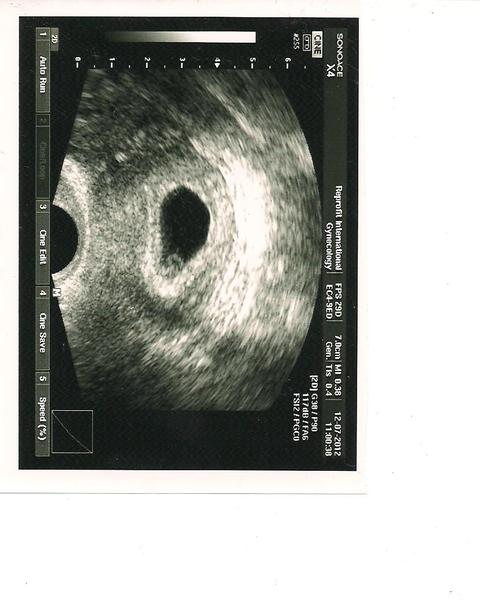

Ahoj děvčátka, děkuji všem za podporu 🙂 Máme srdíčko!!!!! 😵 😵 😵

Dr. byl nějaký roztěkaný a že prý je na fotku brzy, ale já ji vyžebrala, tak ofotím a vložím. Za 2 týdny kontrola opět v Olomouci a pak, pokud ok, mě předají mému Dr. Byly jste taky víckrát v RF na ultrazvuku, než jste se rozloučily? Šance, že zůstane vše v pořádku, je prý 95%. Tak se snažím být optimista 🙂 Ještě jednou děkuji, že jste na mě myslely 🙂